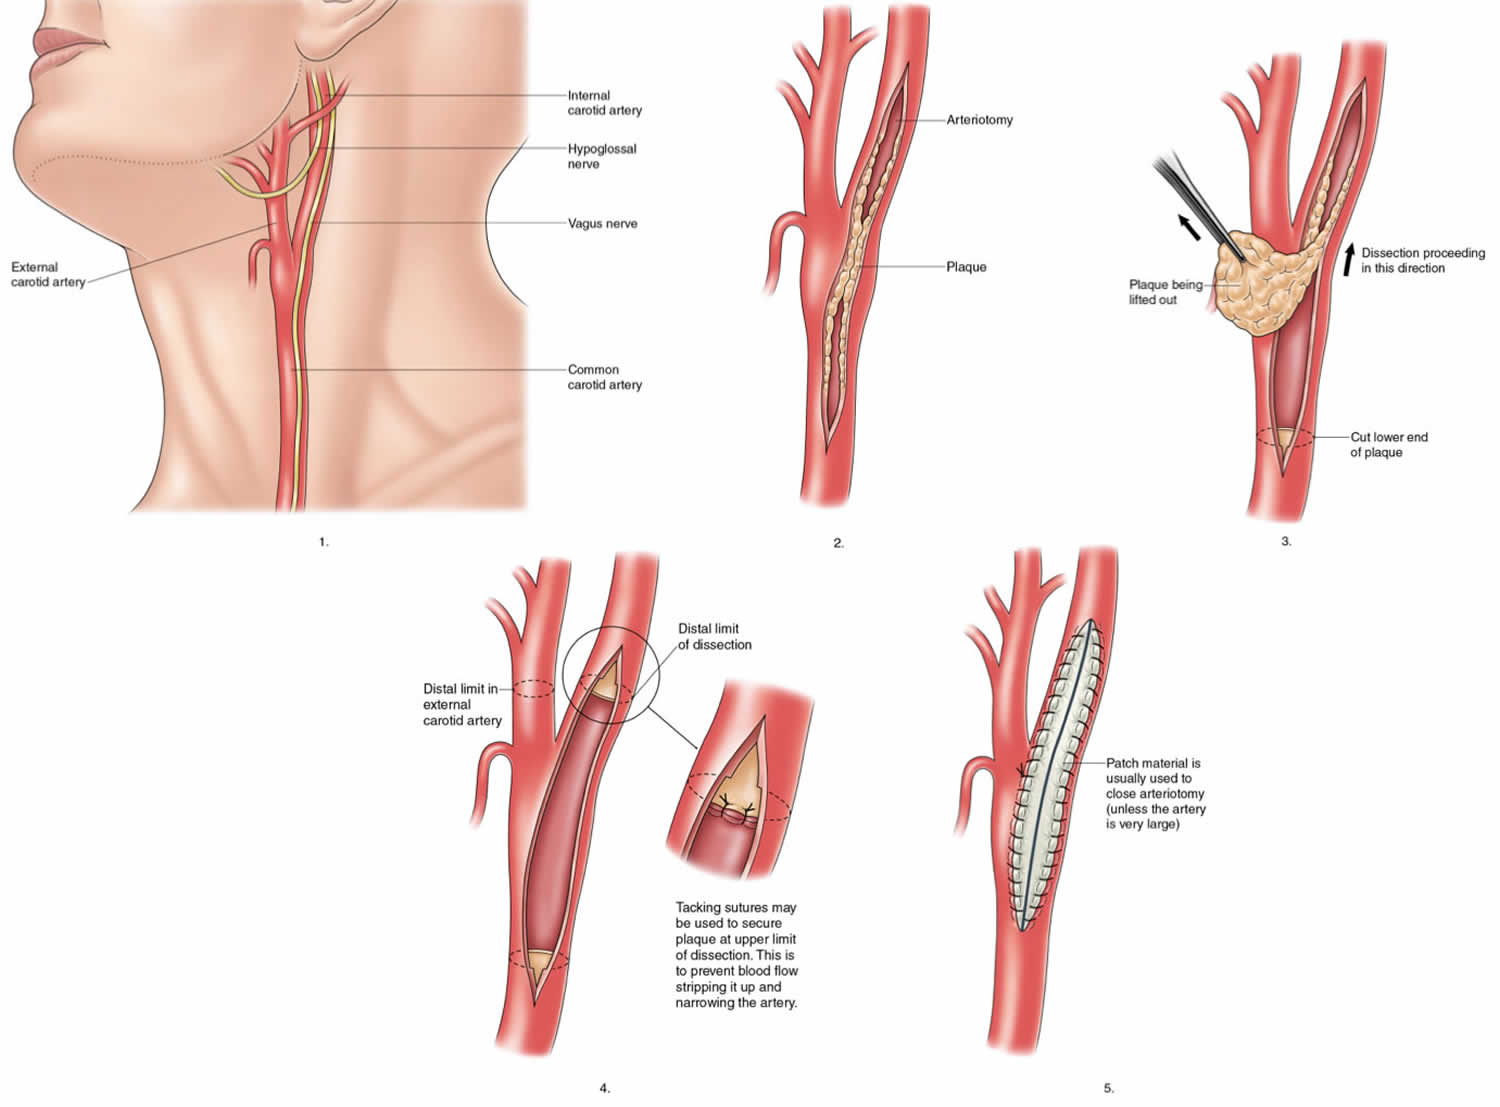

Хроническая окклюзия артерий: причины, симптомы и лечение